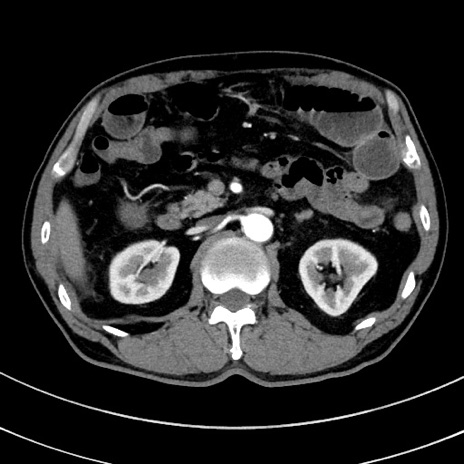

症例8(横断像)

【症例】 60歳代男性

【主訴】 黒色吐物

【現病歴】 4日前から嘔気自覚、2日前の朝食後にも嘔気あり、自分で手で嘔吐反射起こし嘔吐したところ血が混ざっていたため受診。

【既往歴】 5年前汎発性腹膜炎を伴う急性虫垂炎で手術、高血圧、前立腺肥大症、高脂血症

【身体所見】 腹部正中に手術癩痕あり 腹部平坦・軟圧痛なし膨満感あり

【データ】WBC 8400、CRP 4.54